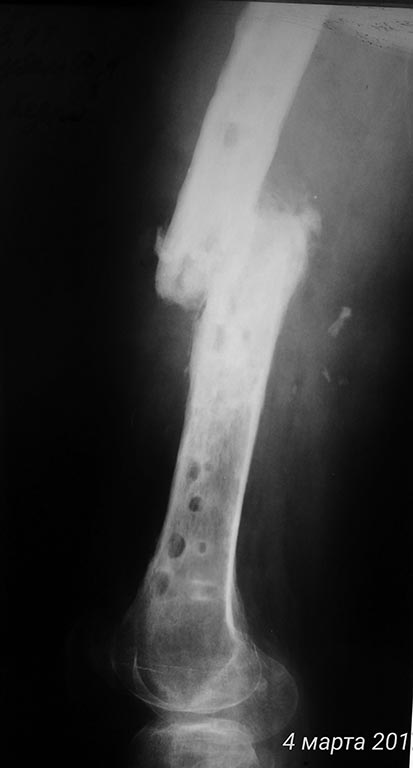

[Ortho] хронический остеомиелит с/3 бедра, свищевая форма, стадия обострения. Несросшийся перелом с/3 бедренной кости.

Дополняю рентген архив

Имя     : P_20170304_124417_p.jpg